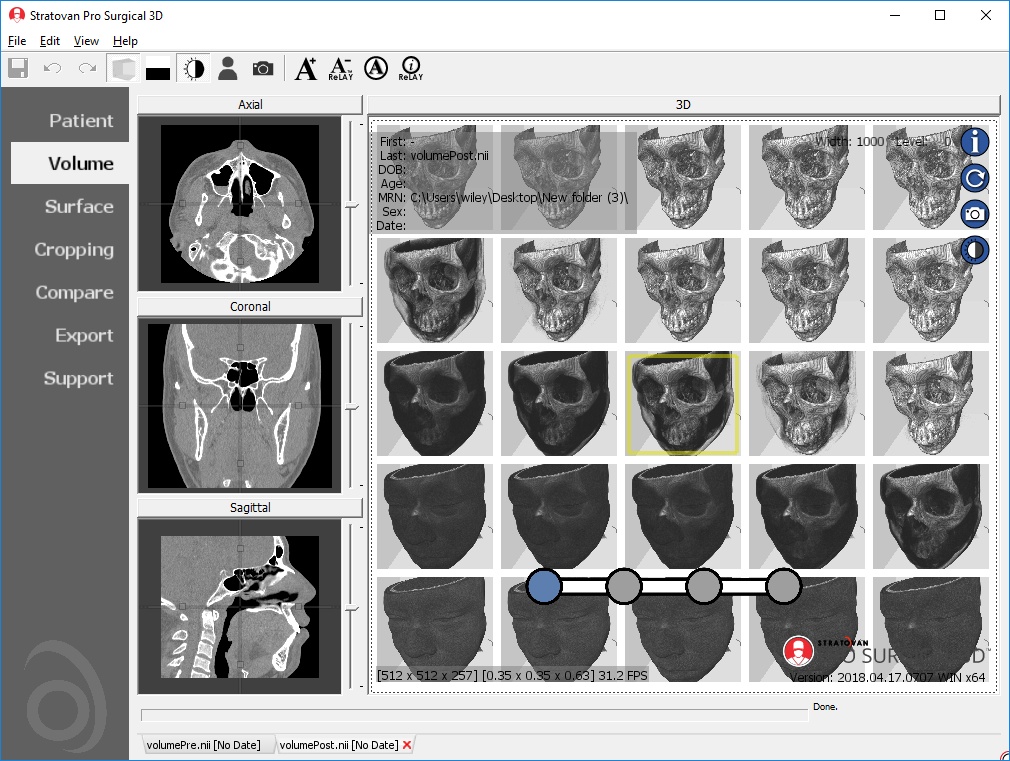

High-quality and fast 3D reconstruction and 3D rendering

Performs 3D reconstruction and volume rendering.

Side-by-side comparative assessment for pre- and post-operative scans.